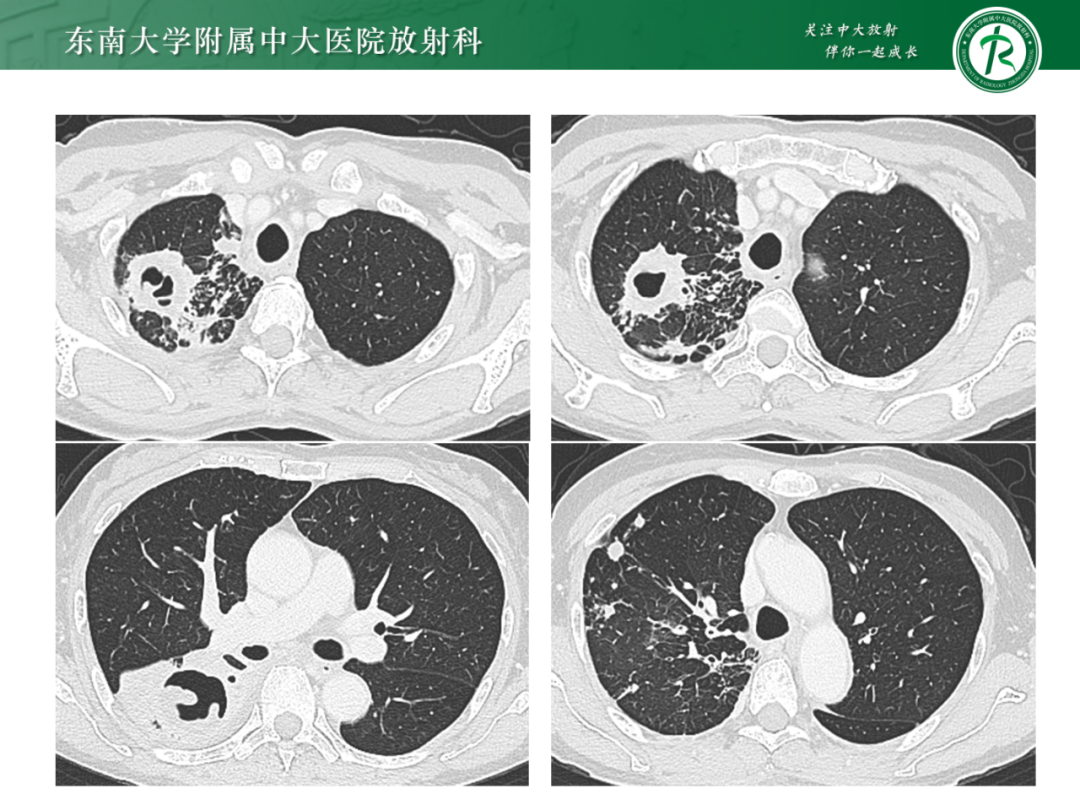

肺多发空洞病例分析|今日病例

作者:东南大学附属中大医院 吕文晖

来源:东南大学附属中大医院放射科